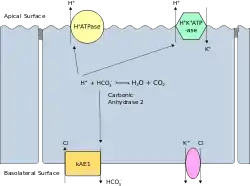

Band 3 is present in the basolateral face of the α-intercalated cells of the collecting ducts of the nephron, which are the main acid-secreting cells of the kidney. They generate hydrogen ions and bicarbonate ions from carbon dioxide and water – a reaction catalysed by carbonic anhydrase. The hydrogen ions are pumped into the collecting duct tubule by vacuolar H+ ATPase, the apical proton pump, which thus excretes acid into the urine. kAE1 exchanges bicarbonate for chloride on the basolateral surface, essentially returning bicarbonate to the blood. Here it performs two functions:

The kidney isoform of AE1, known as kAE1 (which is 65 amino acids shorter than erythroid AE1) is found in the basolateral membrane of alpha-intercalated cells in the cortical collecting duct of the kidney.